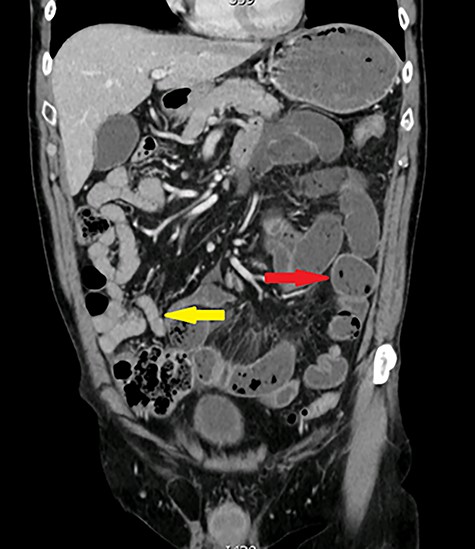

One year later, he was readmitted with small bowel obstruction investigated with an abdominal computed tomography (CT) scan that showed no radiological finding of stenotic Crohn disease or other obstructive etiology (Figs 2 and 3).

Coronal view: arrows pointing to dilated and collapsed small bowel.